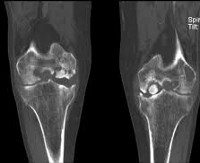

• 1 стадия. Дискомфорт и неясные незначительные боли без четкой локализации. На рентгенограмме выявляется овальное некротизированное тело, отделенное полоской просветления от здоровой кости.

• 2 стадия. Умеренные боли в суставе, явления синовита. Полоса просветления на рентгеновских снимках становится шире. Целостность замыкательной пластинки на поврежденном участке нарушается.

• 3 стадия. Боли, похрустывание и «заедание» сустава. Возможны блокады. На рентгенограммах выявляется некротизированный участок, частично отделившийся от кости.

• 4 стадия. Боли усиливаются, однако блокады становятся более редкими. Отмечается нарастание синовита. На рентгеновских снимках обнаруживается полностью отделившееся внутрисуставное тело.

Диагноз выставляется на основании истории болезни, жалоб пациента, данных физикального обследования и дополнительных исследований. Самым доступным, недорогим и, как следствие, популярным способом инструментальной диагностики является рентгенография. В ряде случаев участок некротизированной кости виден на рентгенограмме. Однако следует учитывать, что область некроза невелика в ряде случаев может не отображаться на снимках. Поэтому отсутствие изменений на рентгенограмме не является основанием для исключения диагноза рассекающий остеохондрит.